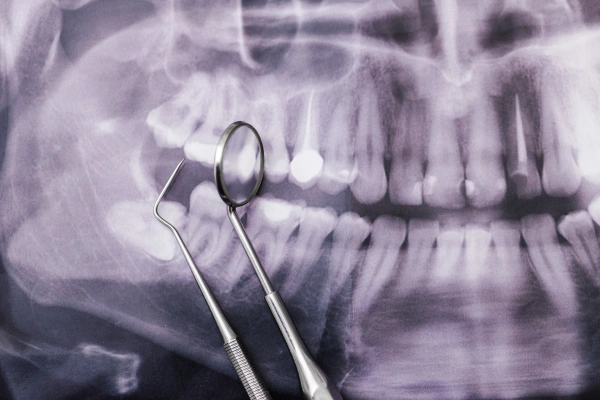

Digital X-Rays & Advanced Planning

Accurate imaging for safe, precise extractions.

Digital X-rays, surgical planning, and precise removal techniques ensure minimal trauma and faster healing.